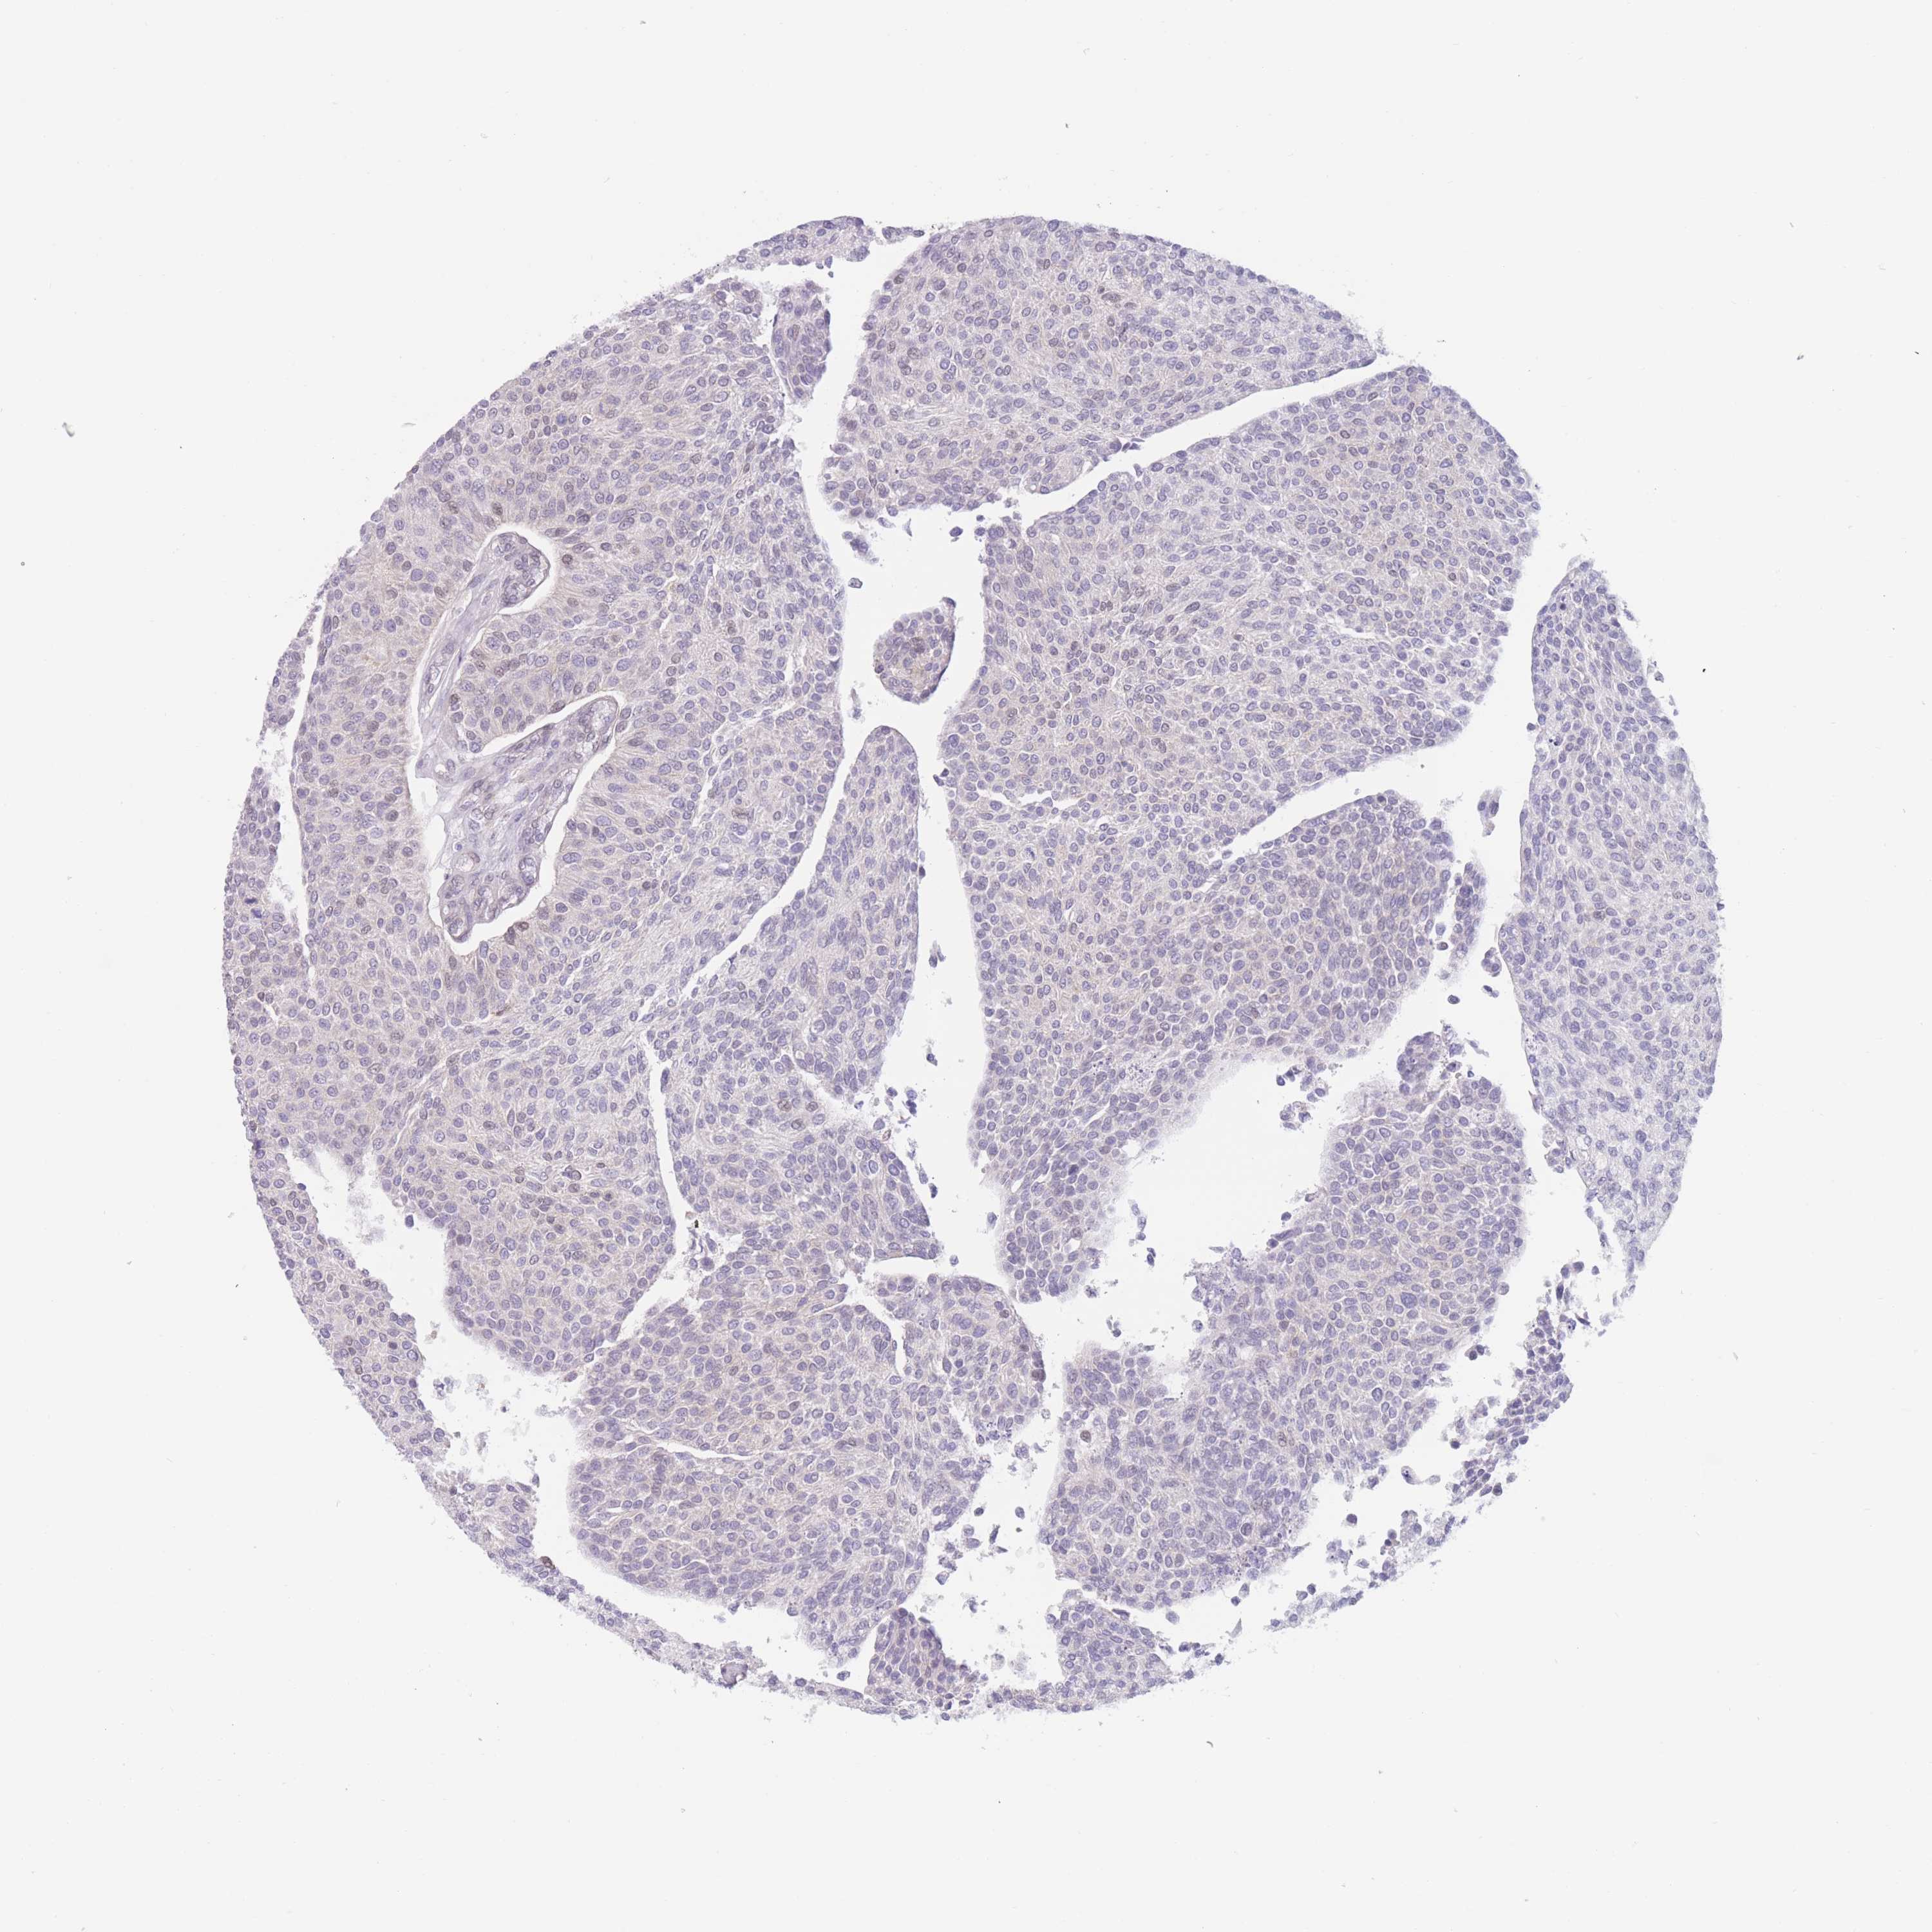

UROTHELIAL CANCER - Protein expressioni

A mouse-over function shows sample information and annotation data. Click on an image to view it in a full screen mode. Samples can be filtered based on level of antibody staining by selecting one or several of the following categories: high, medium, low and not detected. The assay and annotation is described here.

Note that samples used for immunohistochemistry by the Human Protein Atlas do not correspond to samples in the TCGA dataset.

Antibody stainingi

Antibody staining in the annotated cell types in the current human tissue is reported as not detected, low, medium, or high, based on conventional immunohistochemistry profiling in selected tissues. This score is based on the combination of the staining intensity and fraction of stained cells.

Each image is clickable and will lead to virtual microscopy that enables deeper exploration of all samples and also displays staining intensity scores, fraction scores and subcellular localization as well as patient and tissue information for each sample.

HPA002110

HPA045507

CAB016169

CAB062558

CAB068219

CAB068220

Urothelial carcinoma, High grade

Urothelial carcinoma, NOS

Urothelial carcinoma, Low grade